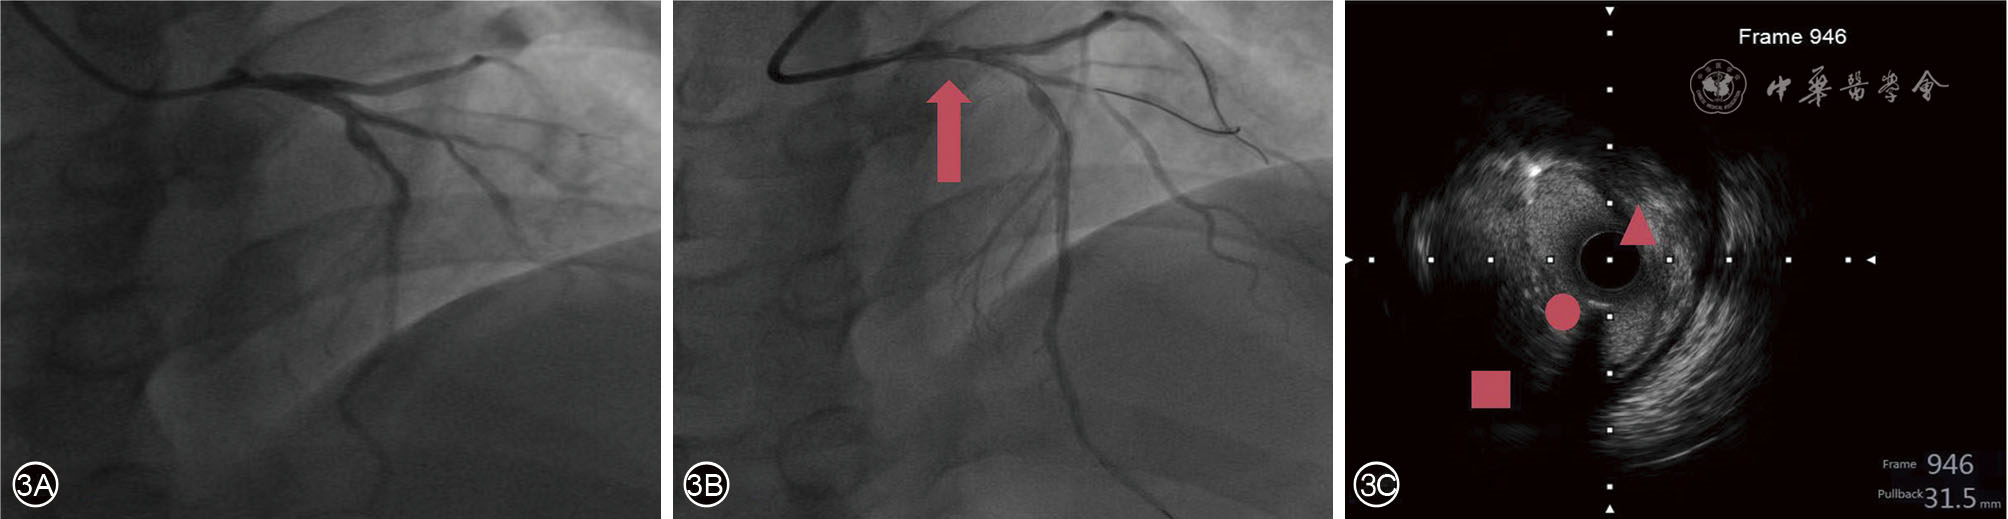

图3 病例2血管内超声及冠脉造影表现 3A:病例2冠脉造影图像;3B:导丝进入冠脉后造影图像,箭头处为冠脉明显狭窄,图3C为病例2 IVUS影像表现,△为椭圆形的管腔狭窄,○为平坦的管壁,□为后部低回声间隙。